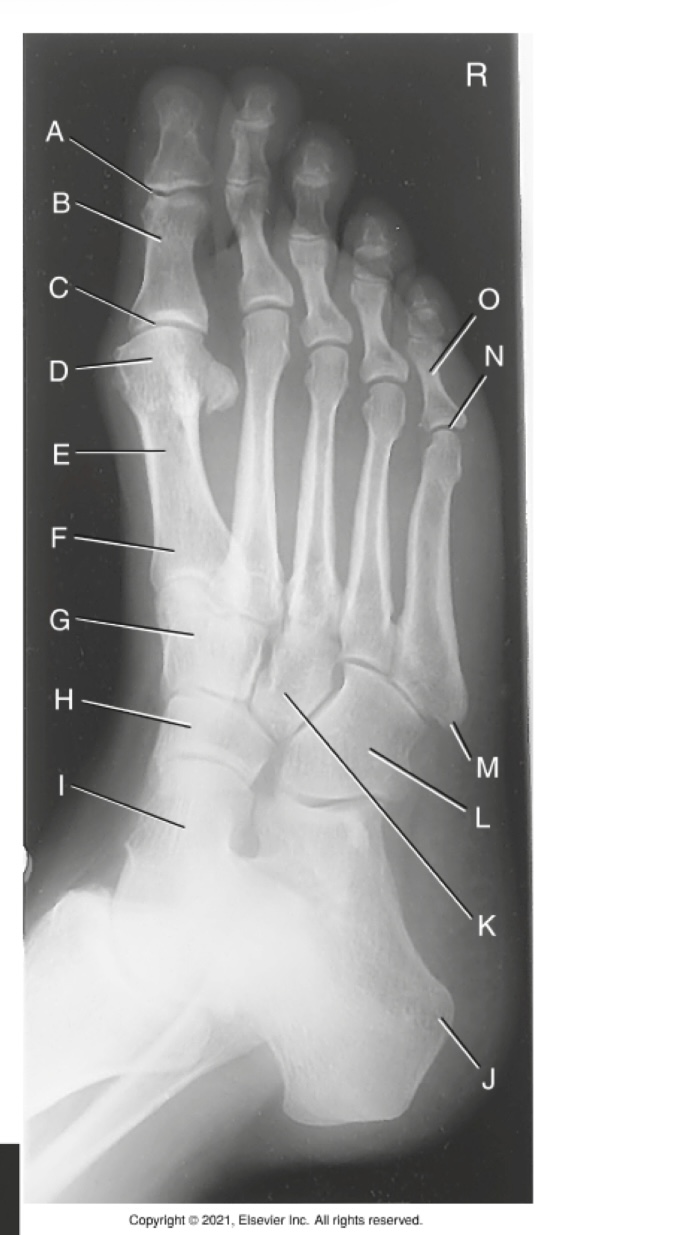

(PA TOES) what is A?

phalanges

what is B?

sesamoids

what is C?

metatarsals

what is D?

Distal interphalangeal joint

what is E?

distal phalanx

what is F?

middle phalanx

what is G?

Proximal interphalangeal joint

what is H?

proximal phalanx

what is I?

Metatarsophalangeal joint